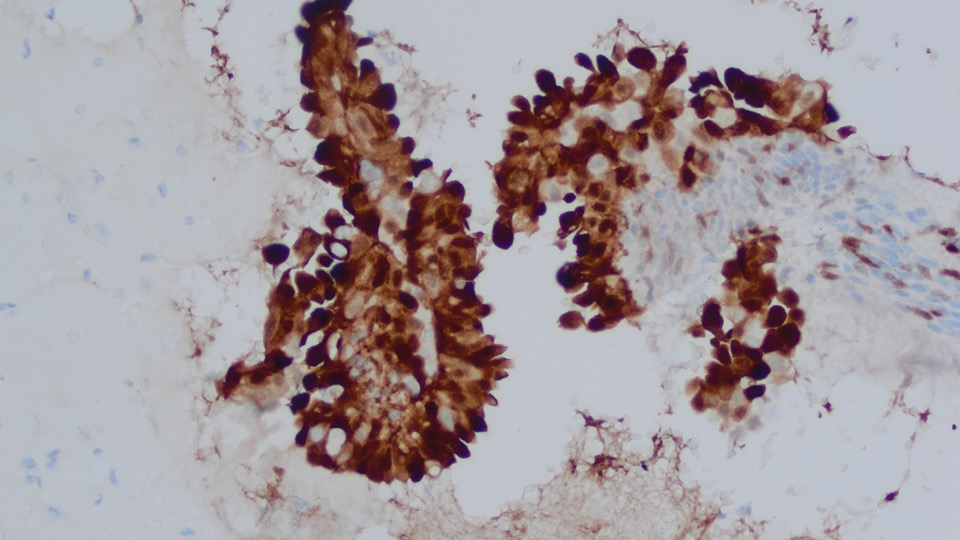

The papillary proliferation is positive for PAX8 (strong), ER (strong scattered), and p16 overexpression; and negative for Napsin A and AMACR. p53 shows wild-type expression pattern.